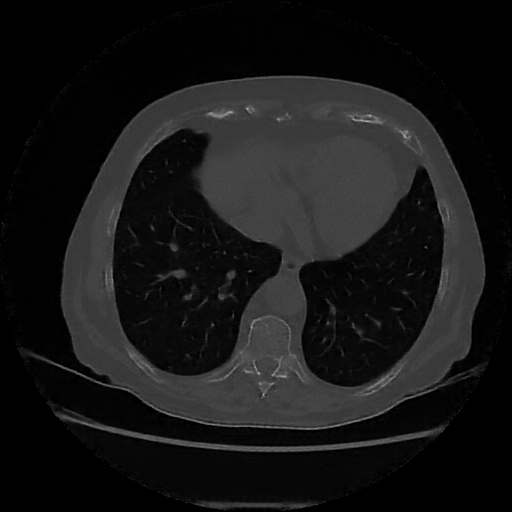

Generated VENOUS CT scan (A→B translation)

Full window (WL 1023.5, WW 4095 β†’ Low βˆ’1024, High +3071)

Lung window (WL -600, WW 1500 β†’ Low βˆ’1350, High +150)